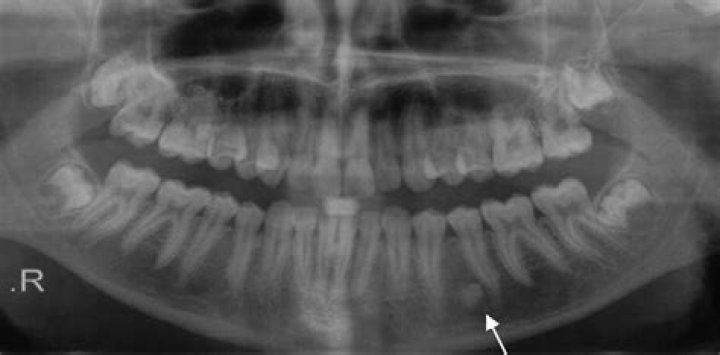

Objectives: Radiopacity of dental materials enables clinician to radiographically diagnose secondary caries and marginal defects which are usually located on